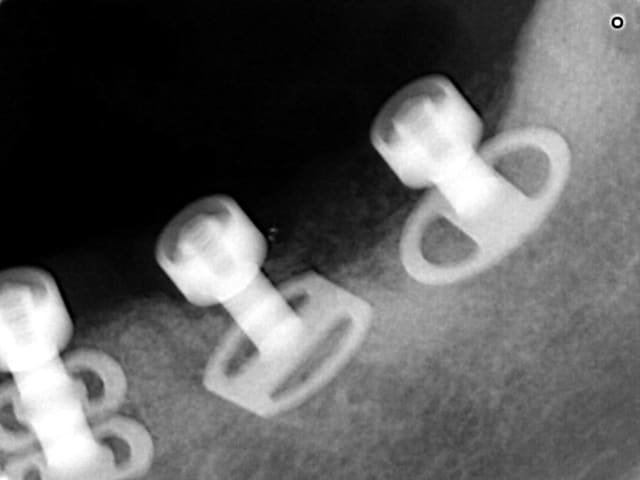

L implant en 45 est le seul rescapé des 8 implants qui lui avait été posé... L ôter revêt un danger supplémentaire de voir cette zonr osseuse encore plus sinistére qu elle ne l a été donc il a été inclus ds le plan de traitement

La zone molaire avait subi une greffe d os mentonnier qui a fondu

L iliaque a fondu sous 5 ans ds le sinus avec perte de qques implants en intrasinusien qu il a bien fallu récupérer là où ils étaient

Apparemment le prothésiste comme le praticien n'ont jamais entendu parlé des notions de "morphologie", "cuspide", "fosse" ou "crête" et ont réalisés un magnifique "bourrelet dentaire plat" sur tout un secteur.

Déjà qu'il s'agit d'un bridge transitoire chez une patiente au maxillaire sinistré dont la rigidité de la travée en L permet d'agir comme un fixateur orthopédique externe pour des implants posés avec une mise en charge immédiate...

Ensuite, on ne fait pas mumuse ici, on sauve une patiente de la prothèse amovible...